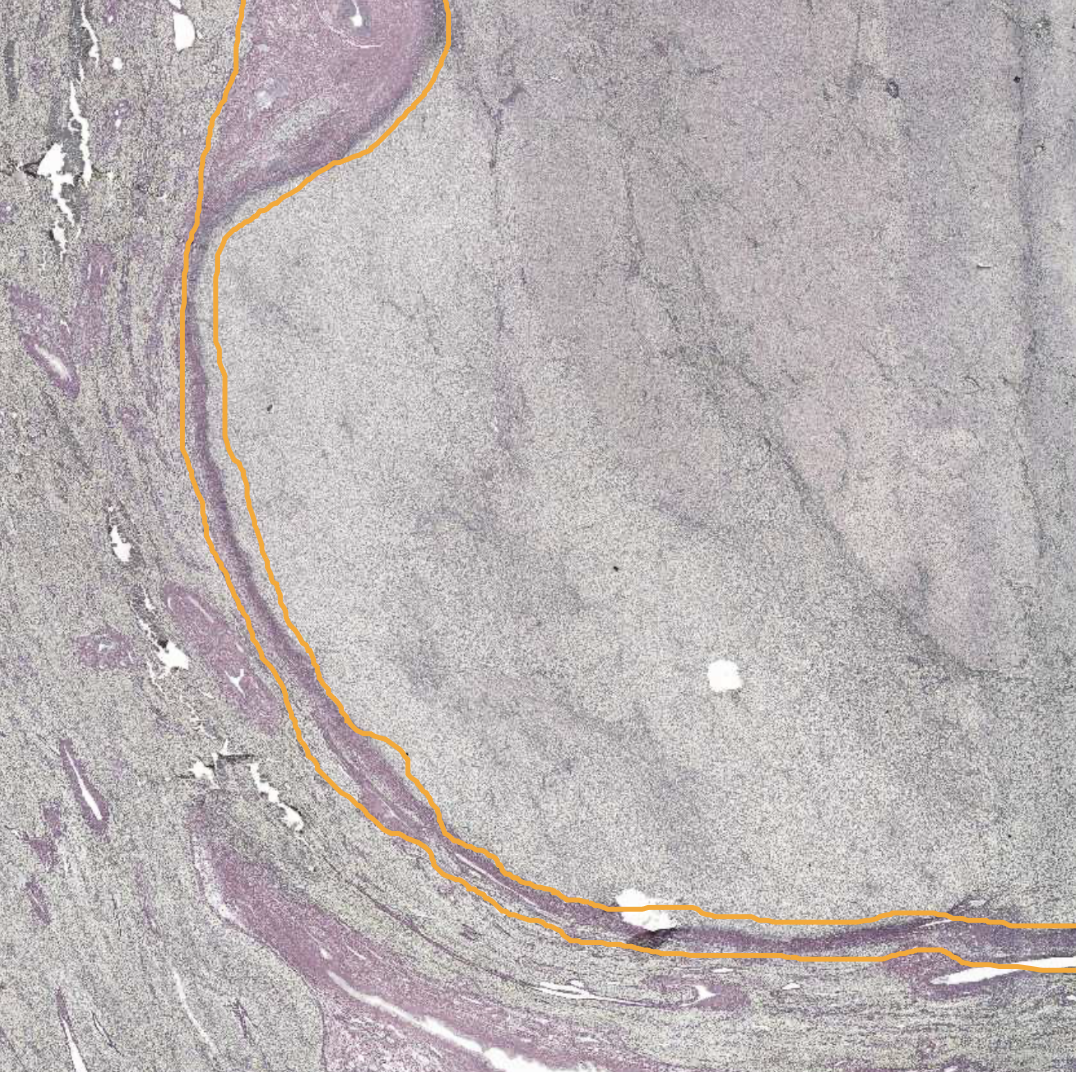

HCC - Capsule surrounding tumour area

Collagen type I

Encapsulates tumor area

Outside pretty much normal liver, inside is tumour and immune cells

Formed by the expansion of the tumour

HCC stained with GoS - Capsule around tumor area

Purple → Collagen type I